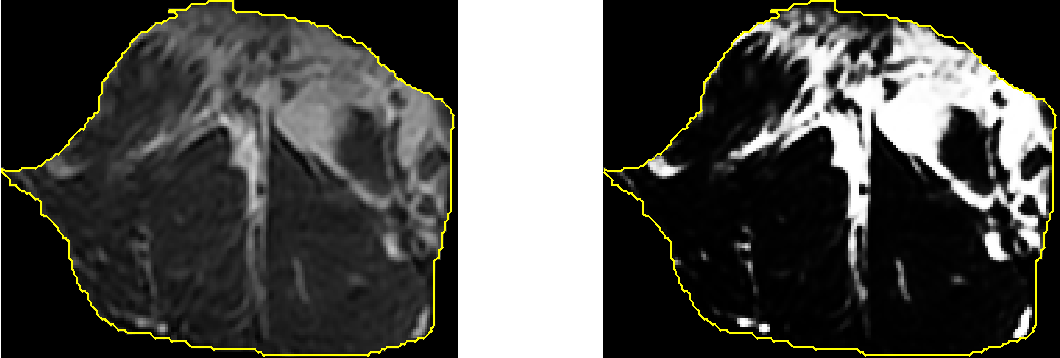

Every pixel in the segmented lumbar muscle region is subjected to the sigmoid function which gives a clear discrimination between the muscle region and the fatty region as shown in Fig. 4.

In the sigmoid function, choosing different values for the centre is associated with the threshold selection for discerning the fatty region from the muscle region. Similarly varying the values of slope control in the sigmoid function is associated with the softness level of the discerned fatty region edges. Pixel belongs to “fat”, if the pixel intensity is above the threshold selected by adjusting the centre value in the sigmoid function .

By calculating the ratio between the number of pixels in the segmented lumbar muscle region to the total pixels in the detected fatty region , the total fat content is calculated.

| (3) |

For example, considering the segmented region shown in Figure 4, the total pixels in the segmented lumbar muscle region were 21,156 and the pixels in the fatty region were 3,733 and the computed total fat content was 17.6 %.